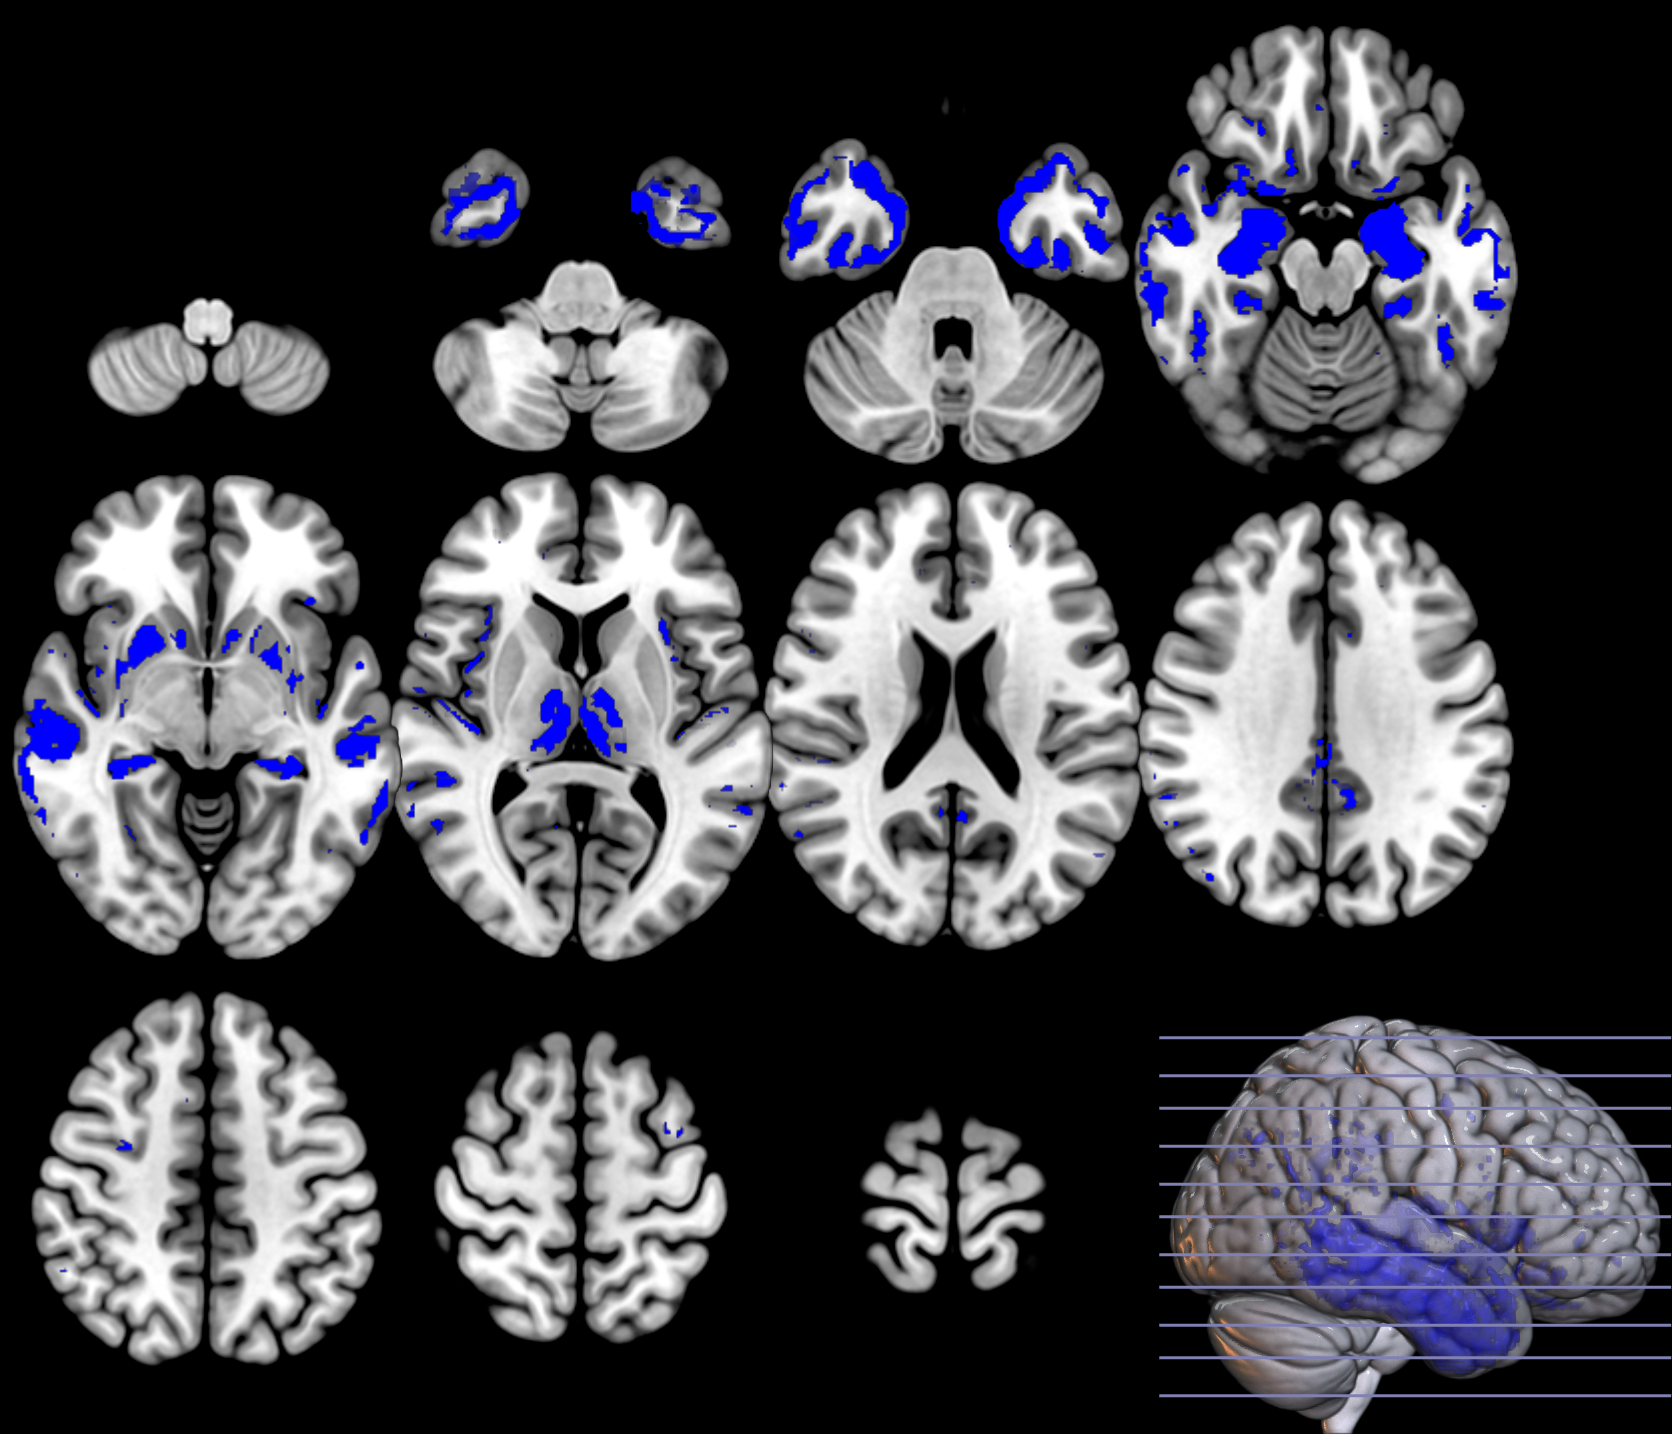

In the last part of this section, we show the inference analysis derived from the two methodologies on each domain. We regress on the observations and on the labels to construct and assess the spatially extended statistical processes, which provide maps of significance, using the MRI ADNI dataset [18]. In this way, we compare SPM, that is based on a two-sample T-statistic similar to equation 3, where significance is individually assessed at each voxel with a using three configurations: cluster-defining threshold CDT of (uncorrected for multiple comparisons), cluster extent threshold equal to and FWE correction at , and the P-tests described in section 2.2.3.

Based on the and values from the original dataset, and the ones obtained using a permutation analysis () for a selection of structures, e.g. hippocampus, we can compare the SPM with the previous inference approaches, as described in section 2.2.3. Note that in this paper the huge amount of voxels contained within an image limits the permutation analysis in this sense to some specific structures. Results on the hipocampus are depicted in figure 13. The permutation analysis reveals how the power of the approach is affected in this featured region, where a real effect might be found in almost the whole structure. The statistical power of the is preserved through the permutation procedure ( detected voxels vs voxels as shown in the same figure). It is also worth mentioning the CDF of the errors derived in the specific region and the distribution of the p-values within it. Recall that the dataset include advanced AD subjects thus the selected structure should be clearly affected by the disease.

To preliminary extend the analysis to the whole volume we approximately simulate the null distribution outside this featured region in two steps. First, we compute the set of p-values in the hippocampus (around voxels) following equation 16 and determine the T threshold that approximately provides the significance level, e.g. . Then, assuming that for any the probability of observation is , we threshold the rest of the image to obtain the significant voxels showing an effect. This approach clearly needs the multiple-comparison correction as several dependent or independent statistical tests are being performed simultaneously at the given significance level. Therefore, we decrease the significance level down to to avoid the presence of false positives in permutation analyses and then compare with SPM in the whole volume using the aforementioned configurations. In figure 13 we show the detection ability together with the control of type I error in the approach (map in red font). Note how the permutation test affects the detection ability of the classical CV approach (map in green font) and how the uncorrected voxelwise SPM approaches (in blue font ) tends to inflate false positives.